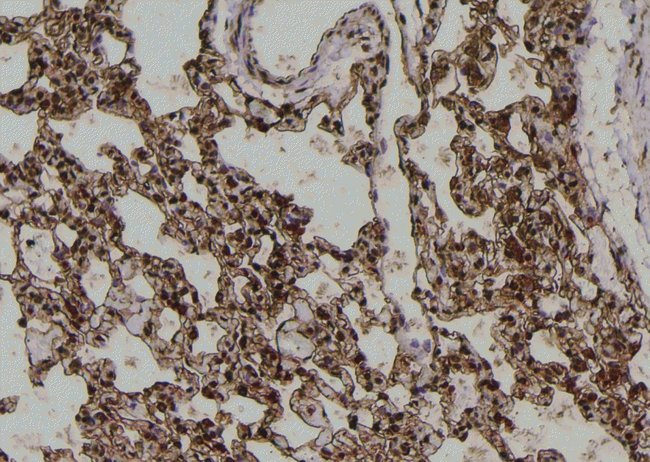

Invitrogen™ Phospho-PKC alpha (Tyr195) Polyclonal Antibody

Antibody detects endogenous levels of PKC alpha only when phosphorylated at Tyr195.

| Immunohistochemistry (Paraffin), Western Blot, Immunocytochemistry | |

| A synthesized peptide derived from human PRKCA(Accession P17252), corresponding to amino acid residues around phosphorylated Tyr195. | |

| Human, Mouse, Rat | |